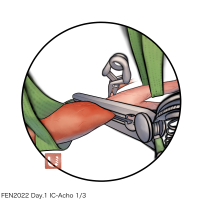

監修:谷川 緑野 / 札幌禎心会病院脳卒中センター

FEN2022シリーズ